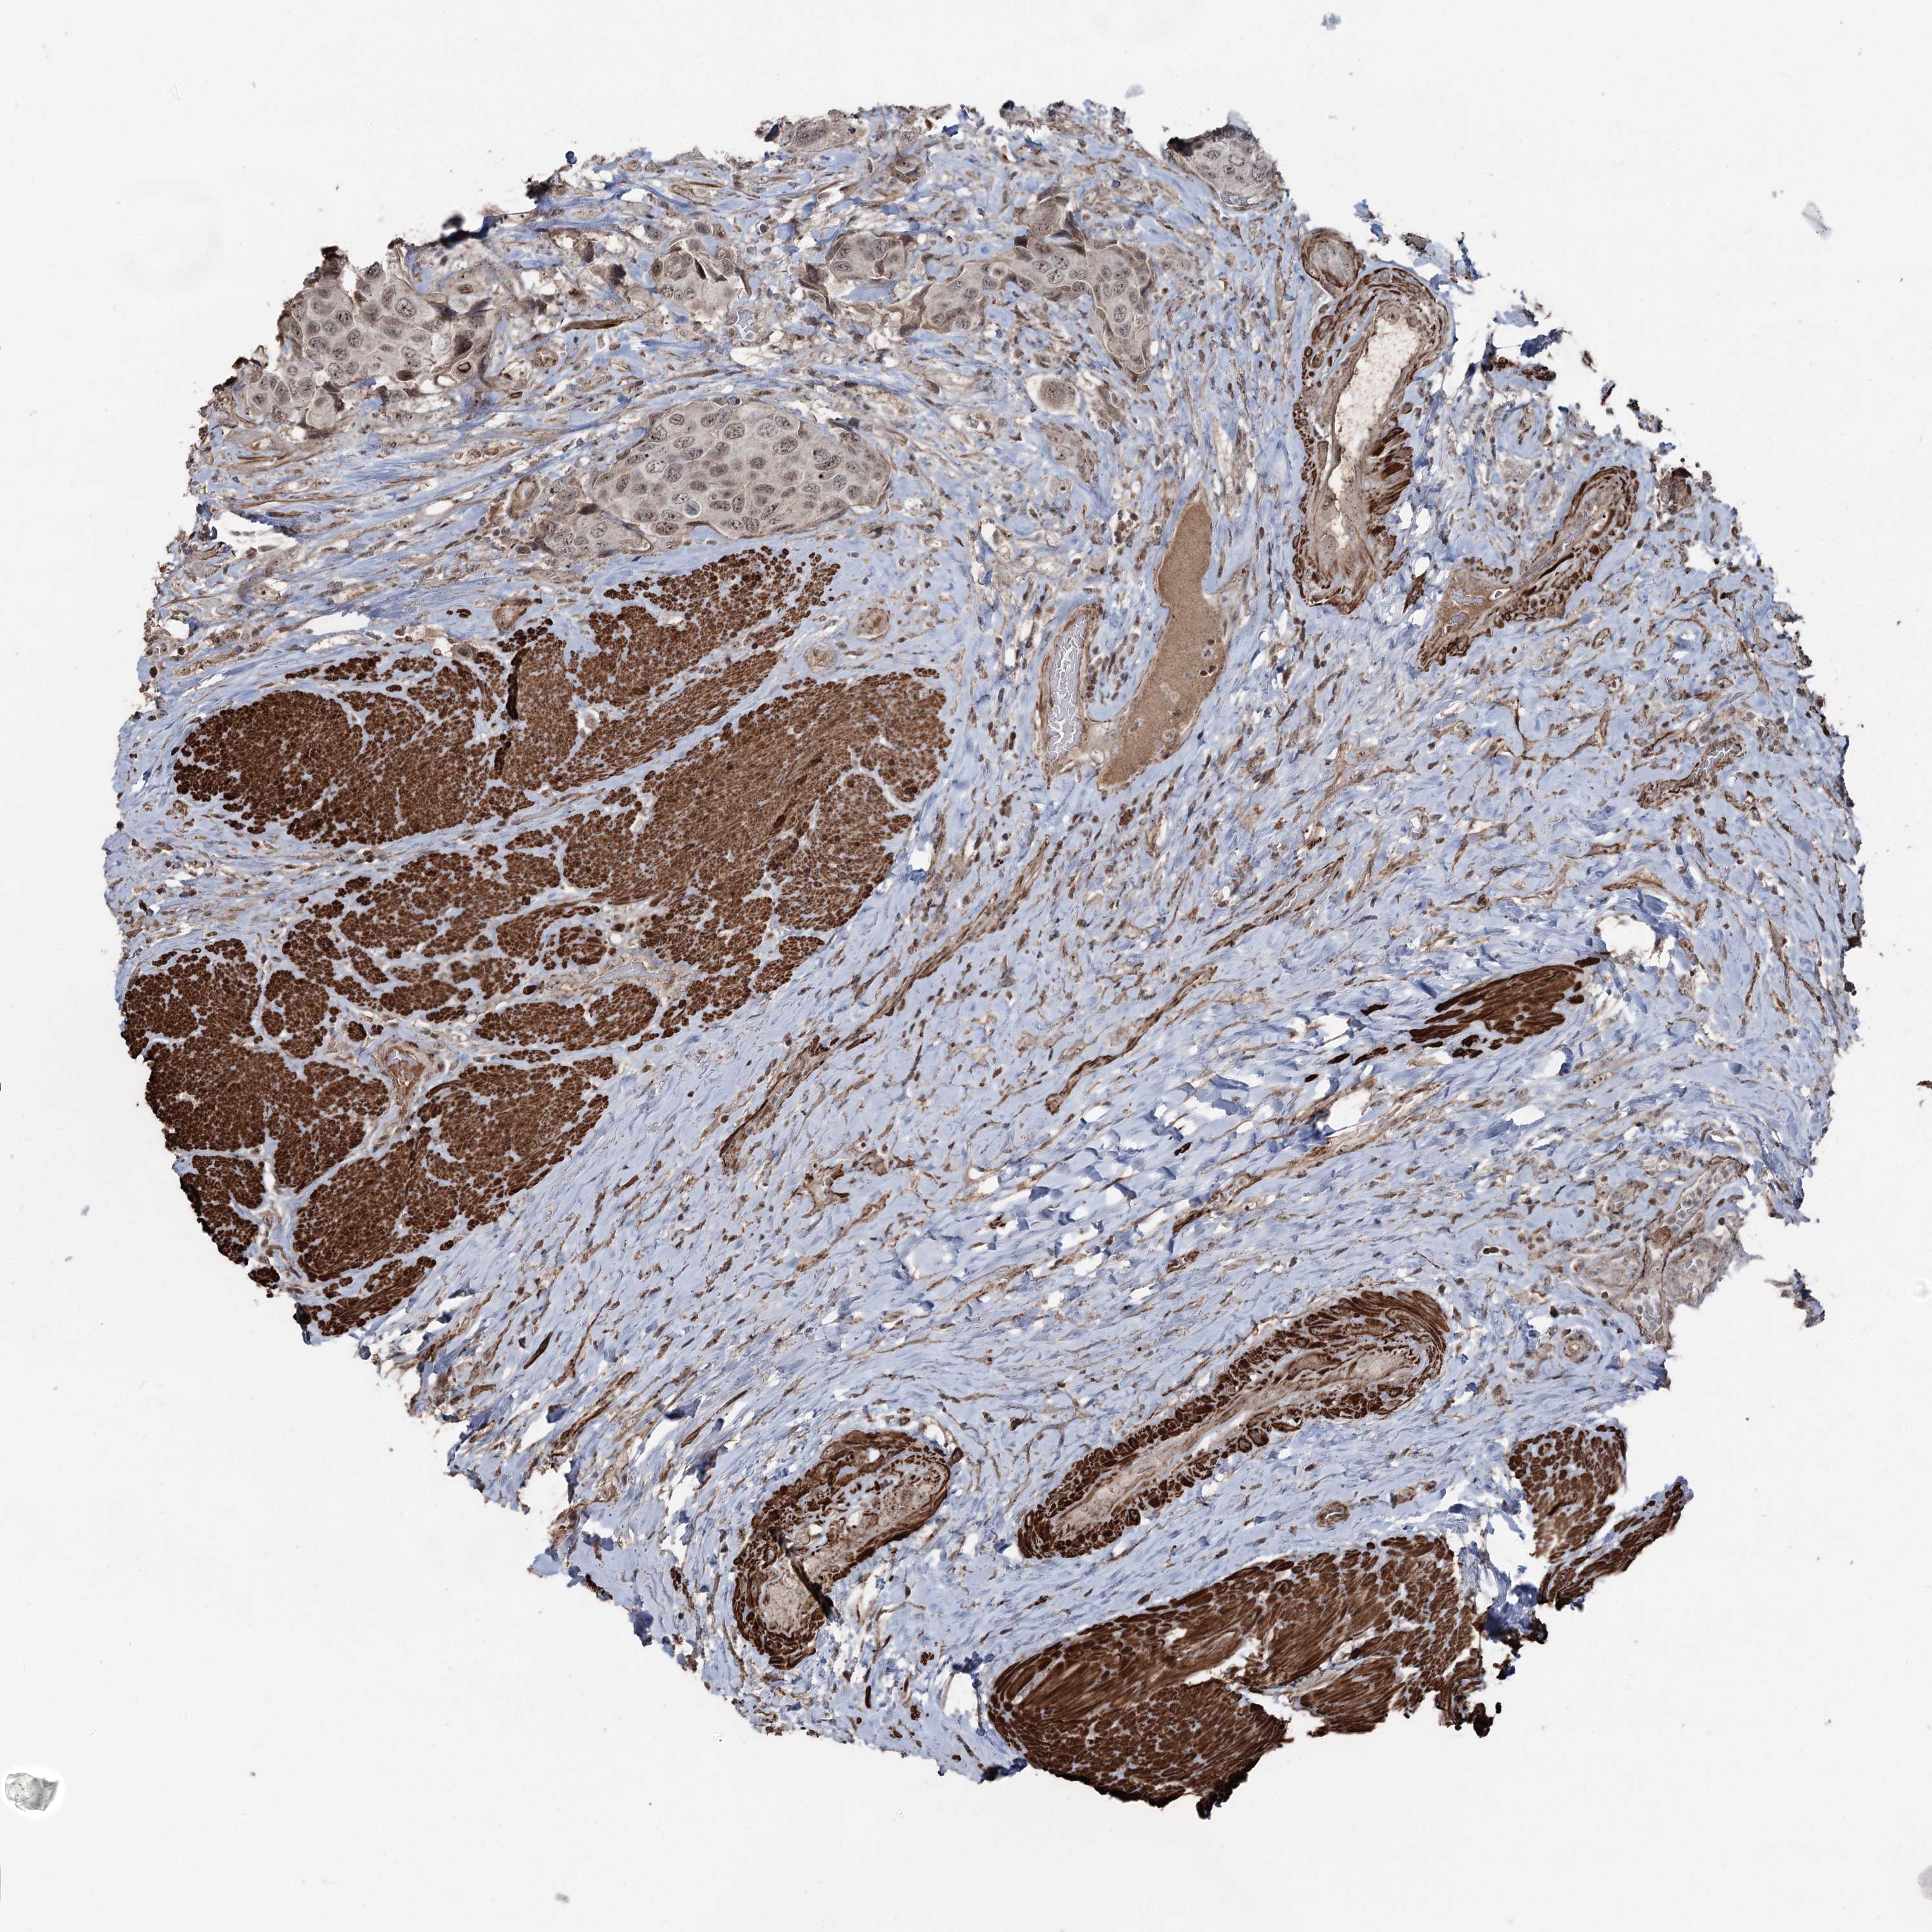

UROTHELIAL CANCER - Protein expressioni

A mouse-over function shows sample information and annotation data. Click on an image to view it in a full screen mode. Samples can be filtered based on level of antibody staining by selecting one or several of the following categories: high, medium, low and not detected. The assay and annotation is described here.

Antibody stainingi

Antibody staining in the annotated cell types in the current human tissue is reported as not detected, low, medium, or high, based on conventional immunohistochemistry profiling in selected tissues. This score is based on the combination of the staining intensity and fraction of stained cells.

Each image is clickable and will lead to virtual microscopy that enables deeper exploration of all samples and also displays staining intensity scores, fraction scores and subcellular localization as well as patient and tissue information for each sample.

Antibody HPA038704

Staining

High

Medium

Low

Not detected

Intensity

Strong

Moderate

Weak

Negative

Quantity

>75%

75%-25%

<25%

None

Location

Nuclear

Cytoplasmic/membranous

Cytoplasmic/membranous,nuclear

Urothelial carcinoma, High grade

Urothelial carcinoma, Low grade